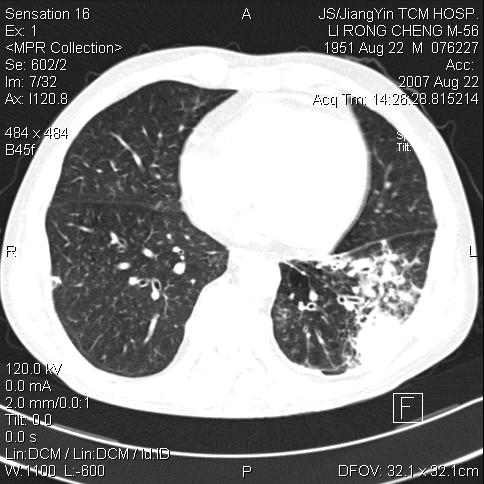

左肺下叶见类软组织密度影,其内密度不均,有小空洞,广基与胸膜相连,其周见斑片状致密影.

考虑肺肿脓,不排除结核.

左下肺团片状类软组织密度影,形态不规则,边缘欠规整,其内可见液化区及气体影,病灶内侧见引流支气管影,相邻胸膜反应性增厚。病灶周围肺野内见增粗支气管,壁厚,边缘模糊。考虑:支气管扩张并感染;肺脓肿。

支持肺脓肿,左下叶见广泛浸润,并见支扩改变。建议治疗后复查。